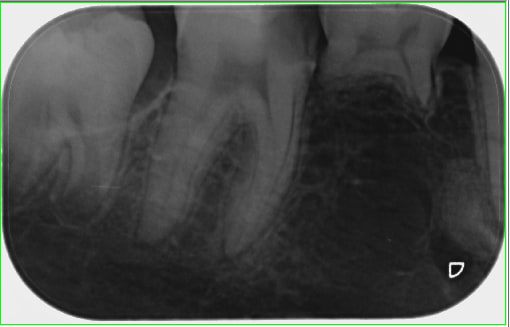

Patiente ado se présentant en consultation pour douleurs légères en bas à droite.

A l'examen, jolie carie 46 (probablement à cause d'une MIH sévère), je fais une radio.

Ooooh surprise la 45.

Vous n'avez pas vu ce qu'il y a près de l'apex de la 44?

> Vous n'avez pas vu ce qu'il y a près de l'apex de la 44?

on dirait un odontome

Cementome, mais la pano nous en dirait plus.

Ou germe ectopique avorté de la 45.

Juste contre le trou mentonnier ...

Bon il n'empèchera pas de poser un clou au moment venu.

Il doit pouvoir rester là où il est.